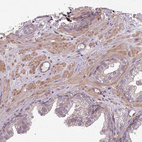

Immunohistochemistry analysis in human tonsil and skeletal muscle tissues using HPA051248 antibody. Corresponding SH3BGRL RNA-seq data are presented for the same tissues.